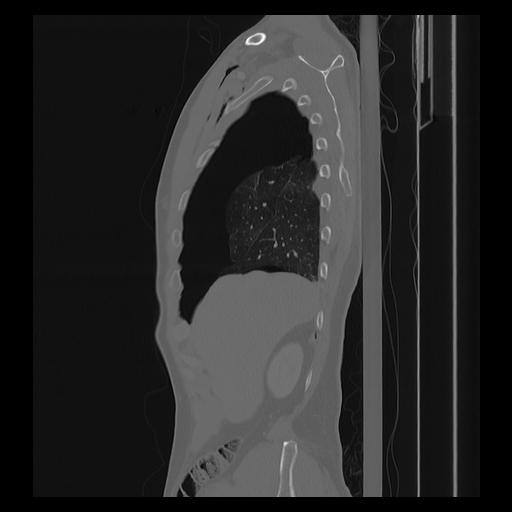

33 PULMON,CE,Sagittal,3.000,PULMON,Sagittal,